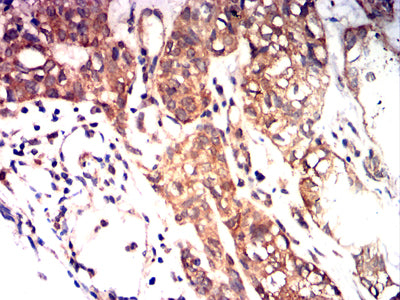

- Immunohistochemical analysis of paraffin-embedded human Bladder cancer tissues using KITLG mouse mAb with DAB staining.